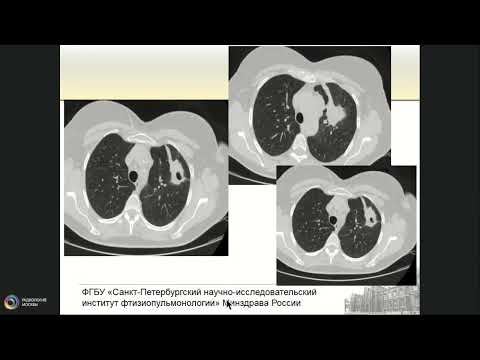

Профессор Сперанская А.А.: Лучевая диагностика туберкулеза органов дыхания